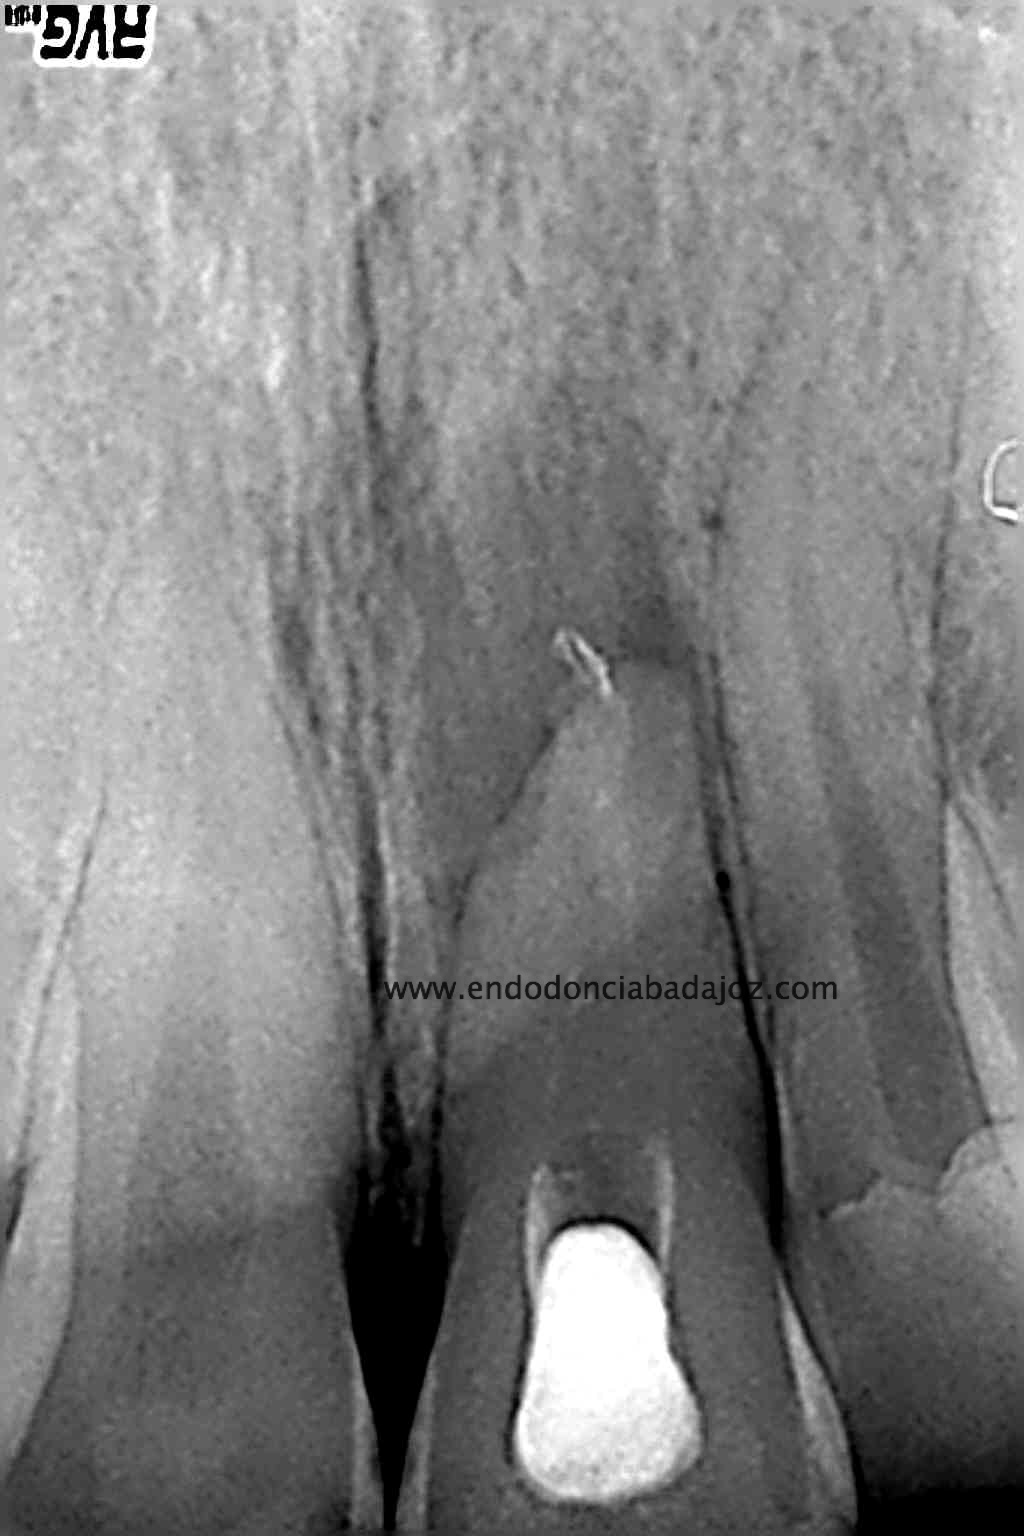

Nos refieren a una chica para retratarle un 2.1, le hicieron un tratamiento de conductos hace unos 5 años y obturaron con pasta. No se recomiendan una obturación con pastas por que no van a conseguir una obturación tridimensional y hermética, y en ocasiones pueden reabsorberse, con lo cual, está contraindicada la obturación solo con pastas.

La paciente presenta un lesión periapical y una tumefacción fluctuante, decidimos retratar.

Intentamos eliminar toda la pasta de las paredes, determinamos el diámetro apical superior a 80, con lo que decidimos actuar colocando una barrera de M.T.A. (Trióxido Mineral Agregado) y hacer un backfilling con gutapercha inyectada.

Lo realizamos en dos sesiones, algo discutido entre compañeros, pero que en este caso, no dudo en absoluto,  pues presentaba una reabsorción apical. Incluso, a la hora de colocar el H de Ca, la medicación intraconducto elegida, decidimos extruirla.